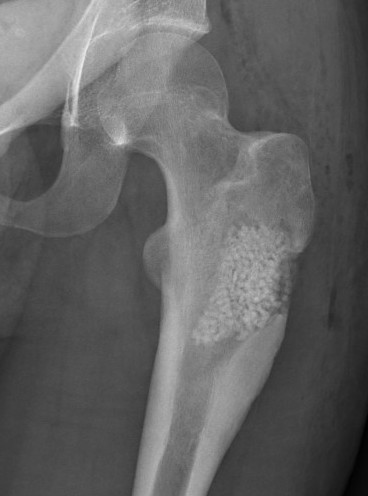

X-ray

Long bone

- more common meta-diaphyseal

- large faintly radiolucent lesion

- thin reactive rim

- may be expansile